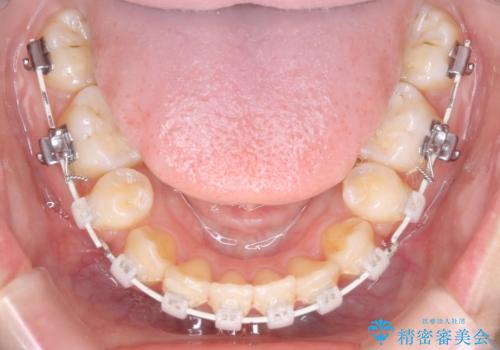

- クリア装置

- 八重歯を主訴に来院されました。4番の歯を4本抜歯し、八重歯を並べる計画をたてました。

抜歯をし、スペースを確保したことにより八重歯をきれいに並べることが出来ました。